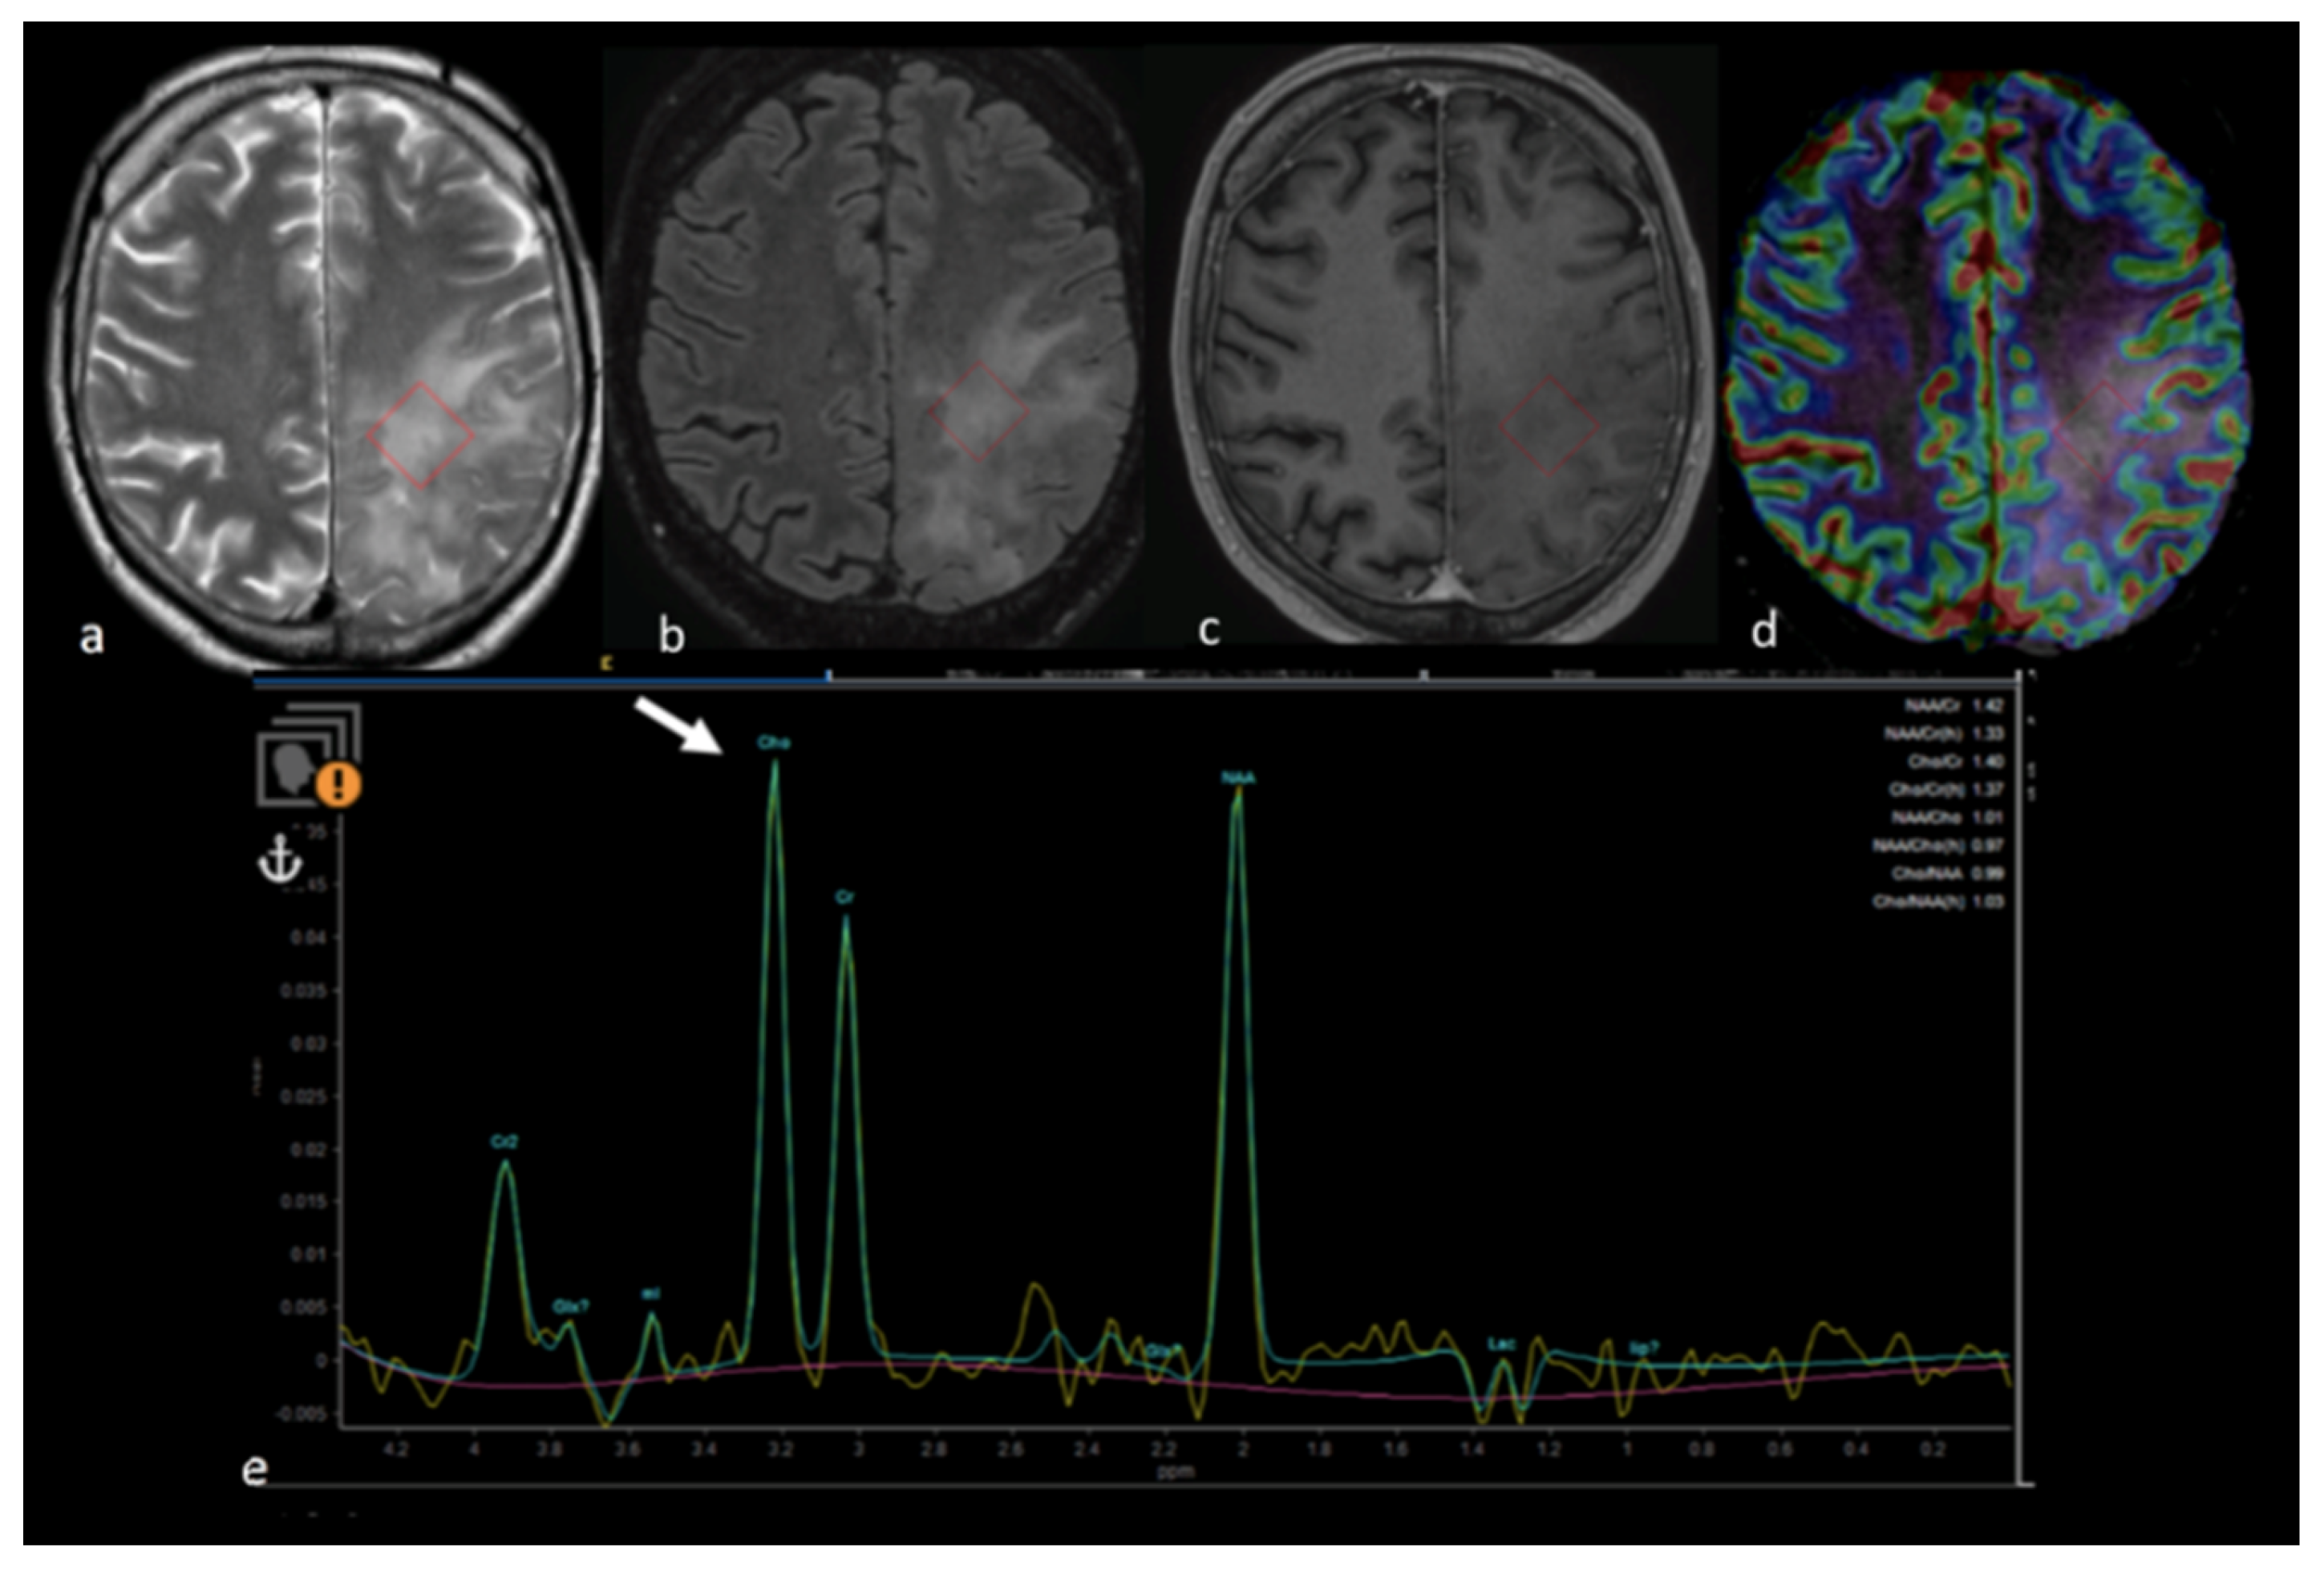

- Chiang, I.C.; Kuo, Y.T.; Lu, C.Y.; Yeung, K.W.; Lin, W.C.; Sheu, F.O.; Liu, G.C. Distinction between high-grade gliomas and solitary metastases using peritumoral 3-T magnetic resonance spectroscopy, diffusion, and perfusion imagings. Neuroradiology 2004, 46, 619–627. [Google Scholar] [CrossRef] [PubMed]

- Bendini, M.; Marton, E.; Feletti, A.; Rossi, S.; Curtolo, S.; Inches, I.; Ronzon, M.; Longatti, P.; Di Paola, F. Primary and metastatic intraaxial brain tumors: Prospective comparison of multivoxel 2D chemical-shift imaging (CSI) proton MR spectroscopy, perfusion MRI, and histopathological findings in a group of 159 patients. Acta Neurochir. 2011, 153, 403–412. [Google Scholar] [CrossRef] [PubMed]

- Wijnen, J.P.; Idema, A.J.; Stawicki, M.; Lagemaat, M.W.; Wesseling, P.; Wright, A.J.; Scheenen, T.W.; Heerschap, A. Quantitative short echo time 1H MRSI of the peripheral edematous region of human brain tumors in the differentiation between glioblastoma, metastasis, and meningioma. J. Magn. Reson. Imaging 2012, 36, 1072–1082. [Google Scholar] [CrossRef] [PubMed]

- Hattingen, E.; Raab, P.; Franz, K.; Zanella, F.E.; Lanfermann, H.; Pilatus, U. Myo-inositol: A marker of reactive astrogliosis in glial tumors? NMR Biomed. 2008, 21, 233–241. [Google Scholar] [CrossRef]

- Ricci, R.; Bacci, A.; Tugnoli, V.; Battaglia, S.; Maffei, M.; Agati, R.; Leonardi, M. Metabolic findings on 3T 1H-MR spectroscopy in peritumoral brain edema. AJNR Am. J. Neuroradiol. 2007, 28, 1287–1291. [Google Scholar] [CrossRef]